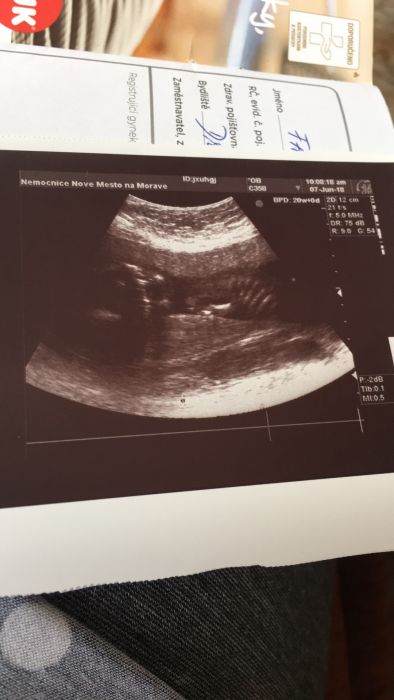

Tak holky kontrola mi dopadla dobře. Doktor mě pořádně zkontroloval, neotviram se, čipek v pořádku..Takže mě zkrátka jen prcek hodně tlačí. Dnes mi dělal ultrazvuk až skoro na kosti, jak byl prcek dole. Doslova mi seděl na mocaku :D jinak teda chlapeček potvrzený ;) ráda fotim, tak takto jsme oznámili chlapečka dneska :)

Tady me dala fotku